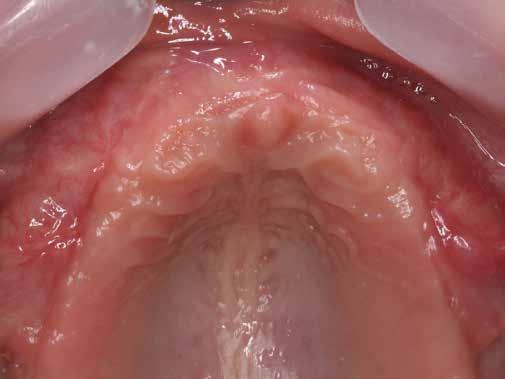

zációt alkalmaztunk (5., 6. ábra). Ezt követően a palatinális marginális gingivát óvatosan alápreparálva a bukkális defektust, valamint az okkluzális felszínt keresztirányban A-PRF membránokkal borítottuk (7. ábra). A mukogingivális lebenyt – annak megnyújtása nélkül – a helyére fektettük és varratokkal rögzítettük, per primam sebzárást nem végeztünk (8., 9. ábra). A varratokat 2 hét után távolítottuk el, a varratszedésig a sebgyógyulás támogatására per os 1000 mg/nap C- és 12 000 NE/nap D-vitamint adtunk (20). A műtéti beavatkozást 24 hét gyógyulási időszak követte, melynek során sem helyi, sem gyógyszeres kezelés nem történt, az esztétikum javítása érdekében a páciens ideiglenes kivehető fogpótlást használt. A csontos gyógyulás ellenőrzése és az implantáció tervezése céljából állcsonti CT felvételt készítettünk, illetve lenyomatvételt végeztünk. A CT felvételen tökéletes csontos gyógyulást észleltünk, az alveolaris csont volumene teljes mértékben megtartott volt (10. ábra), a klinikai kép is ennek megfelelően alakult (11., 12. ábra) A Trishape Implant Studio™ a korábbi csont augmentáció területén, a felső állcsontnál áltagosnak számító D2-D3 csontminőséget jelzett (13. ábra). A lenyomat alapján készített gipszmodellt szkennelve virtuális mintát nyertünk. A CBCT felvétel és a virtuális modell adatait a Dual Scan protokoll (21) elveinek megfelelően használtuk fel az implantációs sablon (New Age Dental Kft, Nemeskéry Károly) készítéséhez (14., 15., 16. ábra). Az implantátum (Ankylos C/X A11) behelyezése teljesen navigált módon, 35 Ncm primer stabilitással történt (17., 18. ábra). Az implantátumra a fogtechnikus (D1 Dental Kft., Garamvári Csaba) által előzetesen elkészített csavarozott, ideiglenes fogpótlást rögzítettünk a gyártó által előírt 15 Ncm-es nyomatékkal, az ideiglenes korona az okklúzióban és artikulációban nem vett részt (19., 20., 21. ábra). A front- és prémoláris régióban, amennyiben lehetséges, mindig nyílt gyógyulási protokollt választunk, azonnali ideiglenes restaurátumot készítve, így biztosítva elegendő időt a lágyrészek maturációjához (23, 24, 25, 26, 27). A kontrollvizsgálatok során havonta ellenőriztük az ideiglenes fogpótlás és az implantátum stabilitását, valamint a lágyrészek állapotát, korrekciós beavatkozás vagy az ideiglenes korona emergencia-profiljának változtatása nem volt szükséges (22. ábra). Két hónapos terhelésmentes időszakot követően, csont-tréninget alkalmaztunk részleges terheléssel, a teljes terhelést a hatodik hónap végére értük el, és megkezdtük a definitív protetikai ellátást. Az ideiglenes restaurátum eltávolításakor az alveoláris struktúrák tökéletes gyógyulását észleltük, a páciens ínye békés, reakciómentes volt, megfelelő mennyiségű keratinizált, feszes ínnyel rendelkezett (23. ábra). Az implantátum stabilitása Periotest-tel -8 értékű volt. Cerec Omnicam rendszerrel digitális lenyomatot vettünk (24. ábra), és a fogtechnikus (Prodont Silver Kft., Panyi János) által ragasztott, csavarozott hibridkerámia koronát készíttettünk nem indexált Ankylos C/ titanium-base fej felhasználásával, amelyet az előírás szerinti 15 Ncm-es nyomatékkal rögzítettünk (25., 26 ábra), majd ellenőriztük az okklúziót és az artikulációt (27. ábra). A beavatkozást követően 6 hónappal az alveoláris struktúrák stabilak, a röntgenfelvételen a csontállomány megtartott, a beteg panaszmentes, rágó funkciója kifogástalan, az esztétikai eredménnyel teljes mértékben elégedett (28., 29., 30. ábra)